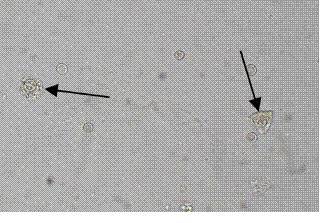

1.箭头所指名称:胆固醇结晶

2.箭头所指名称:脂肪滴